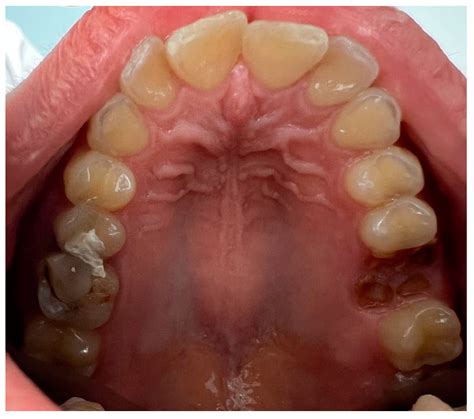

Torus mandibularis refers to a bony outgrowth, or exostosis, that develops along the lingual aspect (the side near the tongue) of the mandible, or lower jawbone. These growths are essentially dense, cortical bone covered by a thin layer of mucosal tissue. When browsing Torus Mandibularis images, you will typically observe that they appear as rounded, hard, and sometimes lobulated projections located above the mylohyoid line, usually in the area of the premolars.

Identifying these growths involves understanding their physical properties. Because they are composed of healthy, dense bone, they feel rock-hard to the touch and are immobile, as they are part of the jawbone itself. Here are the primary characteristics often depicted in Torus Mandibularis images:

• Location: Typically found on the lingual (tongue) side of the lower jaw, most commonly near the premolar teeth.

• Surface Texture: Can be smooth, nodular, or irregular in shape.

For most individuals, torus mandibularis is harmless and requires no treatment at all. You should leave the growth alone if it does not interfere with your daily life. However, dentists may recommend removal in specific clinical scenarios:

• Prosthodontic Needs: If you need to wear a removable denture, the bony growth may interfere with the fit, causing irritation or preventing the denture from seating correctly.

• Periodontal Health: If the growth is so large that it makes it impossible to clean around the nearby teeth, it can lead to plaque accumulation, gum disease, and tooth decay.

While you may find many Torus Mandibularis images online that look remarkably similar to what you see in your own mirror, you should never attempt a self-diagnosis. What appears to be a torus could potentially be an abscess, an oral cyst, or another type of growth that requires a different treatment path. A dental professional uses a combination of clinical inspection and, if necessary, dental radiographs (X-rays) to confirm the diagnosis. Because tori are made of dense bone, they show up clearly as opaque, white masses on X-rays, allowing your dentist to distinguish them definitively from soft-tissue lesions.